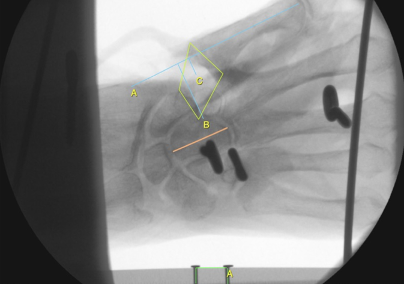

Material und Methoden: 24 paarige fresh-frozen Unterarmpräparate wurden in Neutralpostition fixiert, eine Bewegung im Daumensattelgelenk war frei möglich. Anstatt des Index wurde ein polyaxialer Sensor platziert, Zielwerte waren ein Key Pinch von 12,5 – 25 Newton. Zur Simulation des Key Pinch wurden von definierten Muskeln die physiologischen Kraftvektoren erhalten und mit definierten Gewichten belastet. In a.p. und 30° Röntgen wurde die Höhe nach Trapezektomie zwischen der Basis von MC I und dem Os scaphoideum bestimmt, sowie eine experimentelle Flächenbestimmung durchgeführt. Der Key Pinch wurde drei mal in Folge simuliert. Mit Hilfe es Polyaxialen Sensors konnten Kraftunterschiede und Achsabweichungen dedektiert werden.

Ergebnisse: Der Key Pinch war innerhalb der dreimaligen Messwiederholung ohne signifikante Unterschiede reproduzierbar. Es gab einen signifikanten Unterschied bei den radiologischen Vermessungen der OP-Methoden zugunsten des Mini TightRope. Mittels paired t-Test zeigten beide OP-Methoden im direkten Vergleich signifikante Unterschiede in der Mean Differenz der Röntgen bei allen drei Messungen, ohne Belastung, unter Zug der Extensoren, beim Key Pinch. Es gab keinen signifikanten Unterschied zwischen streng a.p. und 30° geschwenkten Röntgenaufnahmen, sowie der Flächenbestimmung im Vergleich zum Nativröntgen. Die Inter-rater Reliabilität betrug 97%, die Intra-rater Reliabilität betrug 96%. Bei den Sensorauswertungen zeigten sich bei beiden OP-Methoden keine signifikanten Unterschiede zwischen alleiniger Trapezektomie und nach operativer Versorgung mit der jeweiligen OP-Methode.

Abbildung 1 [Abb. 1]